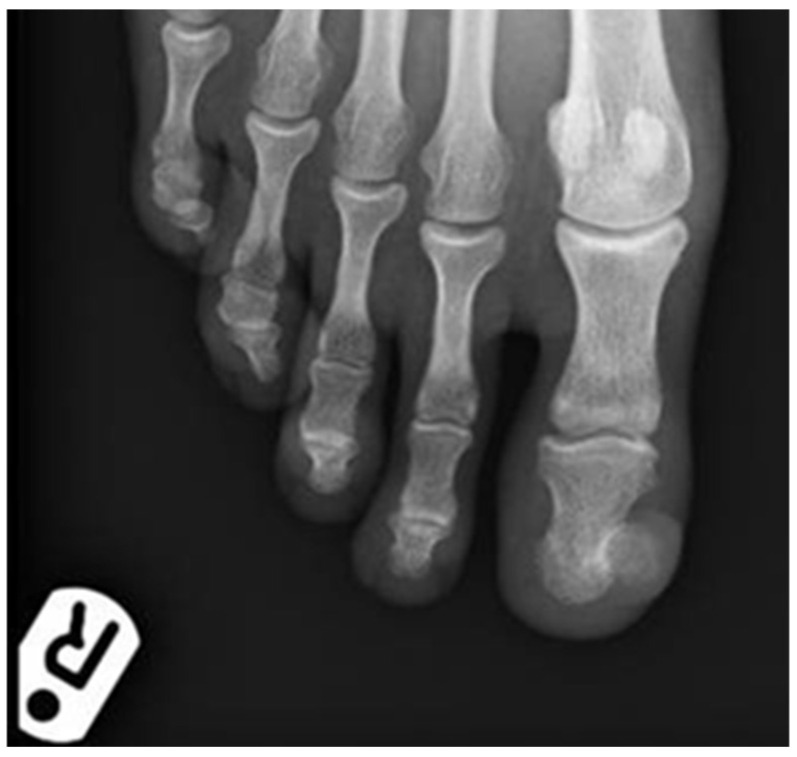

趾骨下外生症(SE)是一种公认的远端指骨的良性增生,最常见于年轻人,影响大脚趾。可能的诱因包括以前的创伤和慢性刺激或感染。我们描述了两个不典型的病例SE在两名年轻女性表现为化脓性肉芽肿样病变的临床。进行诊断活检以确认诊断并排除无色素黑色素瘤。然而,组织学出乎意料地显示反应性肌成纤维细胞增生,类似结节性筋膜炎。鉴于非典型的临床表现,诊断最初被遗漏或没有考虑在两个病人。它们突出了两个要点;首先,se可能在临床上表现为化脓性肉芽肿样病变,需要进行组织学分析以排除恶性肿瘤,特别是无色素黑色素瘤。其次,组织学将显示反应性肌成纤维细胞增殖,如果样本相对肤浅,病理学家没有意识到这种潜在的反应模式,可能会错过SE的潜在诊断。

Subungual exostosis (SE) is a well-recognised benign proliferation of the distal phalanx most often seen in young adults and affecting the big toe. Possible triggers include previous trauma and chronic irritation or infection. We describe two atypical cases of SE in two young women presenting with pyogenic granuloma-like lesions clinically. Diagnostic biopsies were performed to confirm the diagnosis and excluded amelanotic melanoma. However, histology unexpectedly revealed reactive myofibroblastic proliferations mimicking nodular fasciitis overlying the SE. Given the atypical clinical presentation, the diagnosis was initially missed or not considered in both patients. They highlight two important points; the first is that SEs may present with pyogenic granuloma-like lesions clinically and that histological analysis is then required to exclude malignancy, particularly amelanotic melanoma. Secondly, that the histology will show a reactive myofibroblastic proliferation and if the sample is relatively superficial and pathologists are not aware of this potential reaction pattern, the underlying diagnosis of SE may be missed.